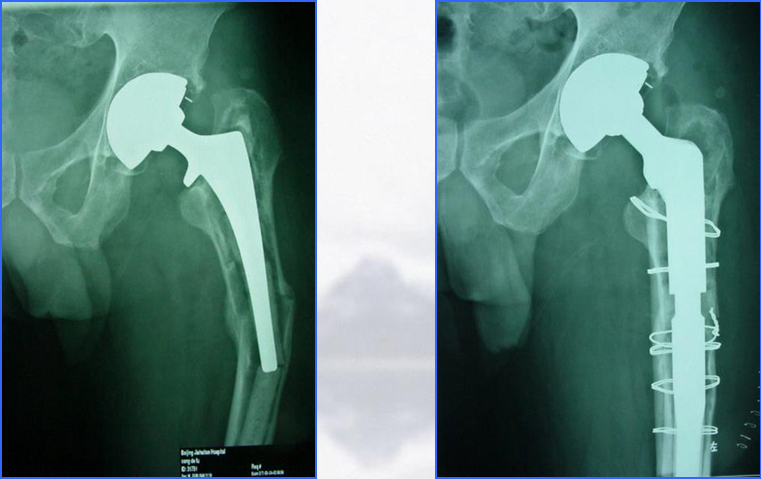

骨缺损者,联合异体皮质骨板髓外固定

髓外固定:(三)异体皮质骨板

优点 :

弹性模量与宿主骨相近 ,作为生物骨板,应力遮挡小

促进骨折愈合

增加宿主骨骨量

容易塑形

缺点 :

费用高

整合过程中机械力量会削弱

异体骨板骨折或不愈合

感染、传播疾病

Emerson:在8.4个月时异体骨板和宿主骨愈合,愈合率96.6%

Haddad:2002年,对40例假体固定良好的股骨假体周围骨折使用了异体骨板固定,骨折98%愈合,而且在术后第一年内有典型的宿主骨异体骨愈合发生